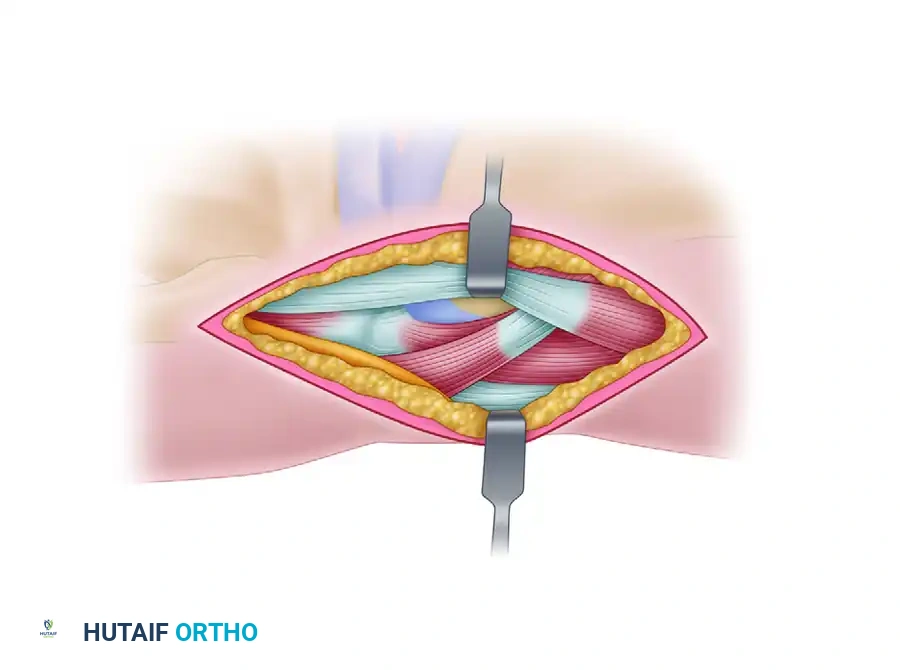

Deep Dissection:

- Continue dissecting through the subcutaneous fat. We'll carefully retract the tibialis anterior tendon laterally.

- Identify the anterior ankle joint capsule.

- Perform a capsulotomy. Use a #15 blade to make a precise longitudinal incision in the anterior capsule, parallel to our skin incision. Extend this carefully proximally and distally to expose the underlying joint.

-

Capsular Stripping and Exposure:

- Using a small periosteal elevator or Freer elevator, meticulously strip enough of the anterior capsule from the distal tibia. Our goal is to expose the medial half of the ankle joint, providing clear visualization of the tibial plafond and the anterior talar dome. This is crucial for planning our osteotomy.

- Place small retractors, such as mini-Hohmanns or Senn retractors, to maintain exposure, ensuring they are not impinging on any neurovascular structures.